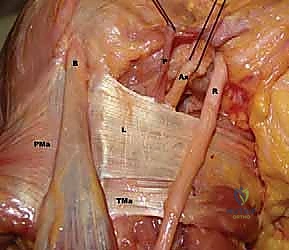

FIG 1 • A. Cadaveric dissection showing the interval between the teres major (TMa) and latissimus dorsi (L) tendons, with the radial nerve (R) deep to the latissimus and the axillary nerve (Ax) superior.

- Axillary Nerve: The axillary nerve runs superior to the latissimus dorsi tendon before exiting the quadrangular space. In neural rotation and adduction, the average distance between the nerve and the superior border of the tendon is 1.9 cm. Like the radial nerve, this distance increases with external rotation and abduction and decreases with internal rotation.

FIG 1 • C. Cadaveric dissection of the superficial muscular anatomy of the posterior shoulder, showing the axillary nerve (Ax) exiting the quadrilateral space.

- Carefully dissect along the superior border of the latissimus dorsi, separating it from the teres major tendon. This is where we need to be acutely aware of the neurovascular structures.

- Crucial Step: Identify the conjoined tendon if present (30% of cases). If so, carefully separate the latissimus from the teres major using sharp dissection.

- Surgeon's Directive: "Maintain constant awareness of the radial nerve. It lies anterior to the latissimus. We'll internally rotate and adduct the arm to increase its distance from our working field, but we must protect it throughout this release."

FIG 4 • B. The latissimus dorsi (L) is identified and separated from the teres major (TMa).